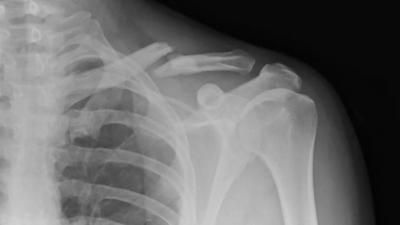

وتشير البروفيسورة إلى أن هشاشة العظام، مرض تبدو فيه العظام وكأنها تذوب، ويقل وزنها، وتفقد قوتها. وتتعرض عدة فئات من الناس لخطر الإصابة بهشاشة العظام: النساء فوق سن 50 عاما، والنساء الحوامل، وكبار السن الذين يعانون من أمراض معينة.

وتقول: "إن أكبر مجموعة من الأشخاص المصابين بهشاشة العظام هم النساء فوق سن 50 عاما. تصاب النساء بالمرض بعد انقطاع الطمث بسبب انخفاض إنتاج الهرمونات الجنسية الأنثوية، هرمون الاستروجين. لأن الطبيعة تحمي أنسجة العظام لدى المرأة الشابة، لأن الكالسيوم يكون ضروريا أثناء الحمل. ولكن بعد 50 عاما، بعد انقطاع الطمث ينخفض مستوى هرمون الاستروجين، وتبدأ التغييرات في أنسجة العظام. ولكن إذا بدأت المرأة أثناء انقطاع الطمث العلاج الهرموني بالهرمونات الجنسية الأنثوية، فلن تتعرض لهذا الخطر".

ولكن هناك حالات تعاني فيها النساء الشابات من هشاشة العظام على خلفية الحمل وإرضاع الطفل. وهذا يدل على أنها كانت تعاني قبل الحمل من نقص العناصر المعدنية في جسمها، وفق روسيا اليوم.

والفئة الأخرى المعرضة لخطر الإصابة بهشاشة العظام هم الأشخاص الذين يعانون من أمراض تؤثر سلبا في العظام.

وتقول: "فمثلا، يمكن أن يكون الانسمام الدرقي - زيادة وظيفة الغدة الدرقية أو فرط نشاط غدة جارة الدرقية. وهذه أمراض روماتيزمية كثيرة، وأمراض الدم والكلى والرئتين. فمثلا يمكن أن تحدث هشاشة العظام بسبب مرض الانسداد الرئوي المزمن، الذي يتطور لدى المدخنين. والقائمة تطول".